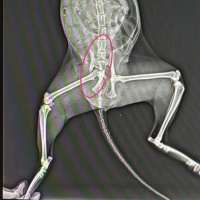

Kedinin röntgen fotosunu aşağıya attım, ben vet doktora gösterdim bana kediye araba güçlü şekilde çaemış dedi ve bir ayağı çalışamaz dedi tamamen kırılmış dedi sadece metal plak takabiliriz iyileşebilirde iyleşmeyebilirde diye söyledi (bu ameliyat metal plak yüzünden aşırı pahalı) başka bir seçenek çalışmayan bacağı ampute etmek. Kedi şu an yere yıöılmış ve haraket etmiyor yemek yemiyor bir tek günlerdir az az su içiyor ve altına yapıyor tuvaletini, yaptığı zaman yaraların üzeride bulaşıyor ve iyileşmesini önlüyor. Ne yapmam gerek kedinin ayağını ampute etseler böyle yaşayabilir mi? normal şekilde yemeğini yer suyunu içip azdan çoktan gezebilir mi? ağrısı hiç değilse azalsın istiyorum, gün günden eriyip gidiyor güzel hayvan.